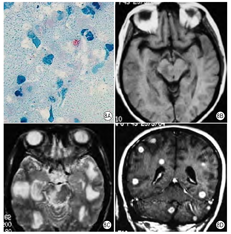

病理改变:CMV感染是由CMV引起的性传播疾病。CMV为DNA病毒。特征性病变为感染细胞增大,细胞核和细胞质内分别出现嗜酸性和嗜碱性包涵体。CMV感染在全世界分布,人是CMV的唯一宿主。不同国家及不同经济状况感染率不同。成人CMV感染和免疫功能有密切关系。多累及肺部及脑部(图4A、图4B)。

影像表现:MRI表现为脑室周围片状长T1长T2信号,也可呈脑白质弥漫小斑片状长T1长T2信号。增强室管膜可出现强化,脑实质无强化(图4C、图4D)。影像诊断没有特异性,脑脊液的CMV DNA的检查对诊断更有帮助[6]。